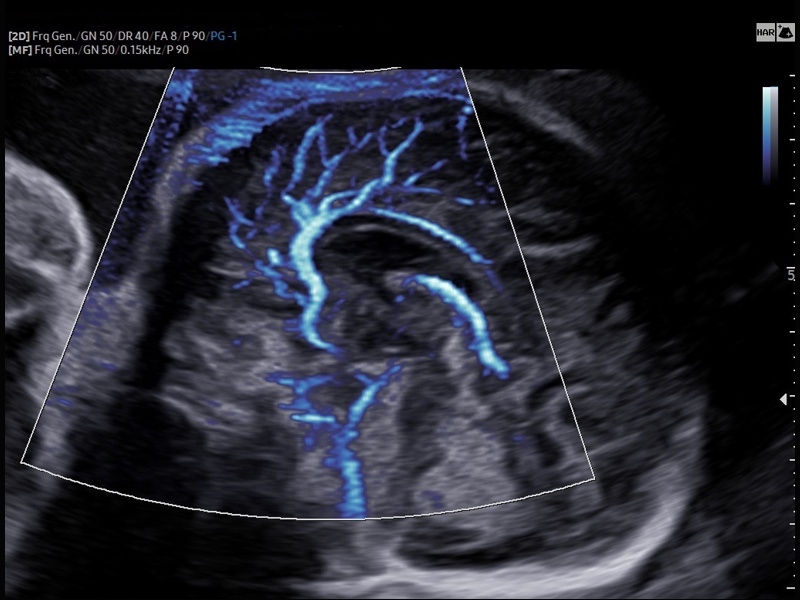

• Модуль MV-Flow – программа (режим), позволяющая визуализировать кровоток в микроциркуляторном русле с высоким разрешением без использования контраста.

• Модуль LumiFlow – программа отображения кровотока с объемной графикой для лучшего понимания архитектоники сосудистого русла.

• Модуль MV-Flow - программа (режим), позволяющая визуализировать кровоток в микроциркуляторном русле с высоким разрешением без использования контраста.